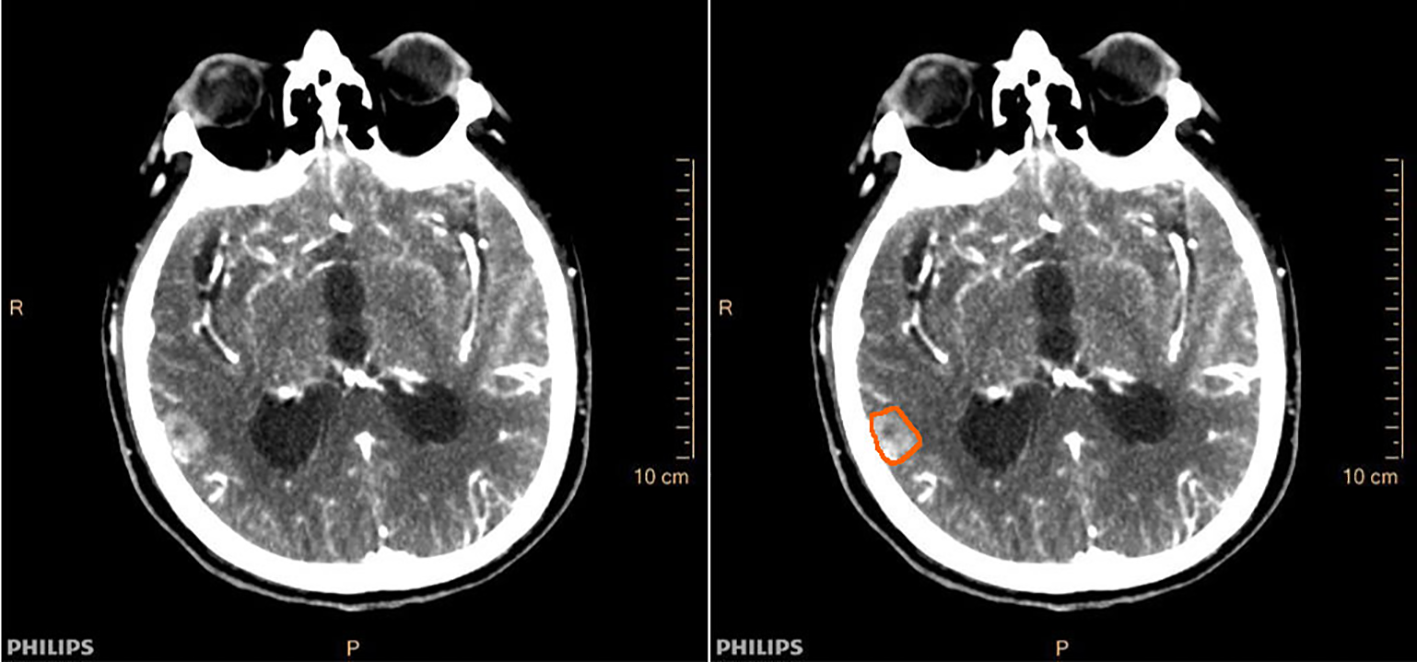

Two independent radiologists outlined the ROIs. One intracranial maximal metastasis was selected for each patient, and ROIs were outlined at the largest level of the metastases and its two consecutive layers above and below. Cases with significant discrepancies in certain subjective outlines were reviewed jointly by the supervising physician until an agreement was reached. Finally, the ROIs outlined by one of the radiologists were selected, and perfusion parameters are obtained by machine operations, including cerebral blood volume (CBV), cerebral blood flow (CBF), mean transit time (MTT), and time to peak (TTP). The averages of the three layers of perfusion parameters for each metastasis were used as the final valid parameters. Figure 2 demonstrated a case of lung adenocarcinoma brain metastasis with CT perfusion images and ROI outlined. To observe the reproducibility of perfusion parameter extraction, we randomly selected 10 patients to perform the intraclass correlation coefficient (ICC) test on the ROI outlined by two radiologists, and ICC ≥0.8 was considered as better reproducibility.

Figure 2

Cranial CT perfusion imaging (left) and region of interest (ROI) outline of intracranial metastases (right) in a patient (male, 78 years old) with brain metastases from lung adenocarcinoma.